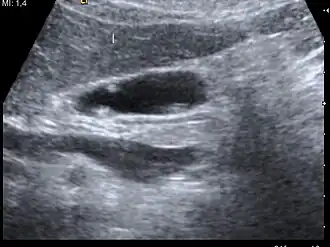

| A polyp in the gall bladder as seen on ultrasound |

Ultrasound image of gallbladder polyps measuring 3–7 mm. -